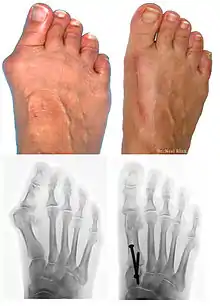

L’hallux valgus (HV, du latin hallus, gros orteil et valgus : « tourné en dehors »), souvent accompagné d'un « oignon » (callosité de la peau en regard de la déformation), est une déformation du pied correspondant à la déviation du premier métatarsien en varus (en dedans) et du gros orteil (hallux) en valgus (en dehors).

L'HV associe plusieurs déformations qui sont :

- un hallux abductus si M1P1 > 20° ;

- un metatarsus varus si M1M2 > 10° ;

- un metatarsus elevatus ;

- une pronation du gros orteil (pas toujours présente).

Ces déformations n’évoluent pas forcément en même temps. De plus, on trouve une exostose, qui peut être très douloureuse, sur le bord médial de la première tête métatarsienne.

Bilan radiographique

Le diagnostic est avant tout clinique, mais des radiographies sont indispensables pour mesurer la déformation et adapter la technique chirurgicale aux spécificités du patient. Les radiographies doivent être effectuées de façon rigoureuse : clichés d'avant-pied de face, profil, et 3/4, patient debout en charge. Ce dernier critère est indispensable car le squelette du pied adopte des positions dans l'espace qui diffèrent selon que le poids du corps repose ou non sur lui. C'est l'état du squelette debout en charge qui doit guider le geste chirurgical.